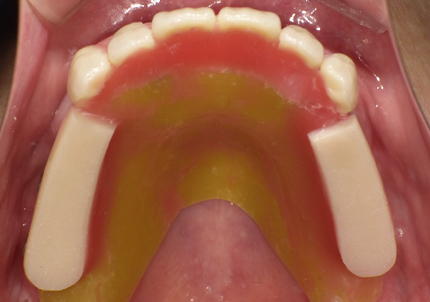

3.サージカルガイド(インプラント埋入用)作製(2019年3月)

7.サージカルガイドによるインプラント埋入手術

8.テンポラリーヒーリングアバットメント装着して仮歯の作製